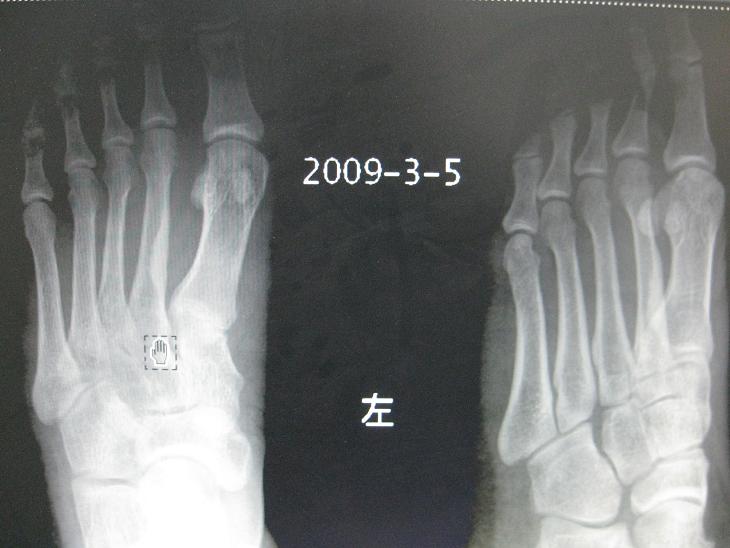

男,26岁,外伤来诊发现第二跖骨骨皮质密度增高,请问这是什么病

如无明显症状,多考虑-----骨内膜局限增生性改变----机体的代谢过程。

如有症状,则需排除---硬化骨髓炎,疲劳骨折后遗期,不典型骨样骨瘤等。

第二跖骨局限性骨皮质增厚。

局限性骨皮质增厚,正常个体表现,为发育生长过程中骨皮质重塑形“不良”形成